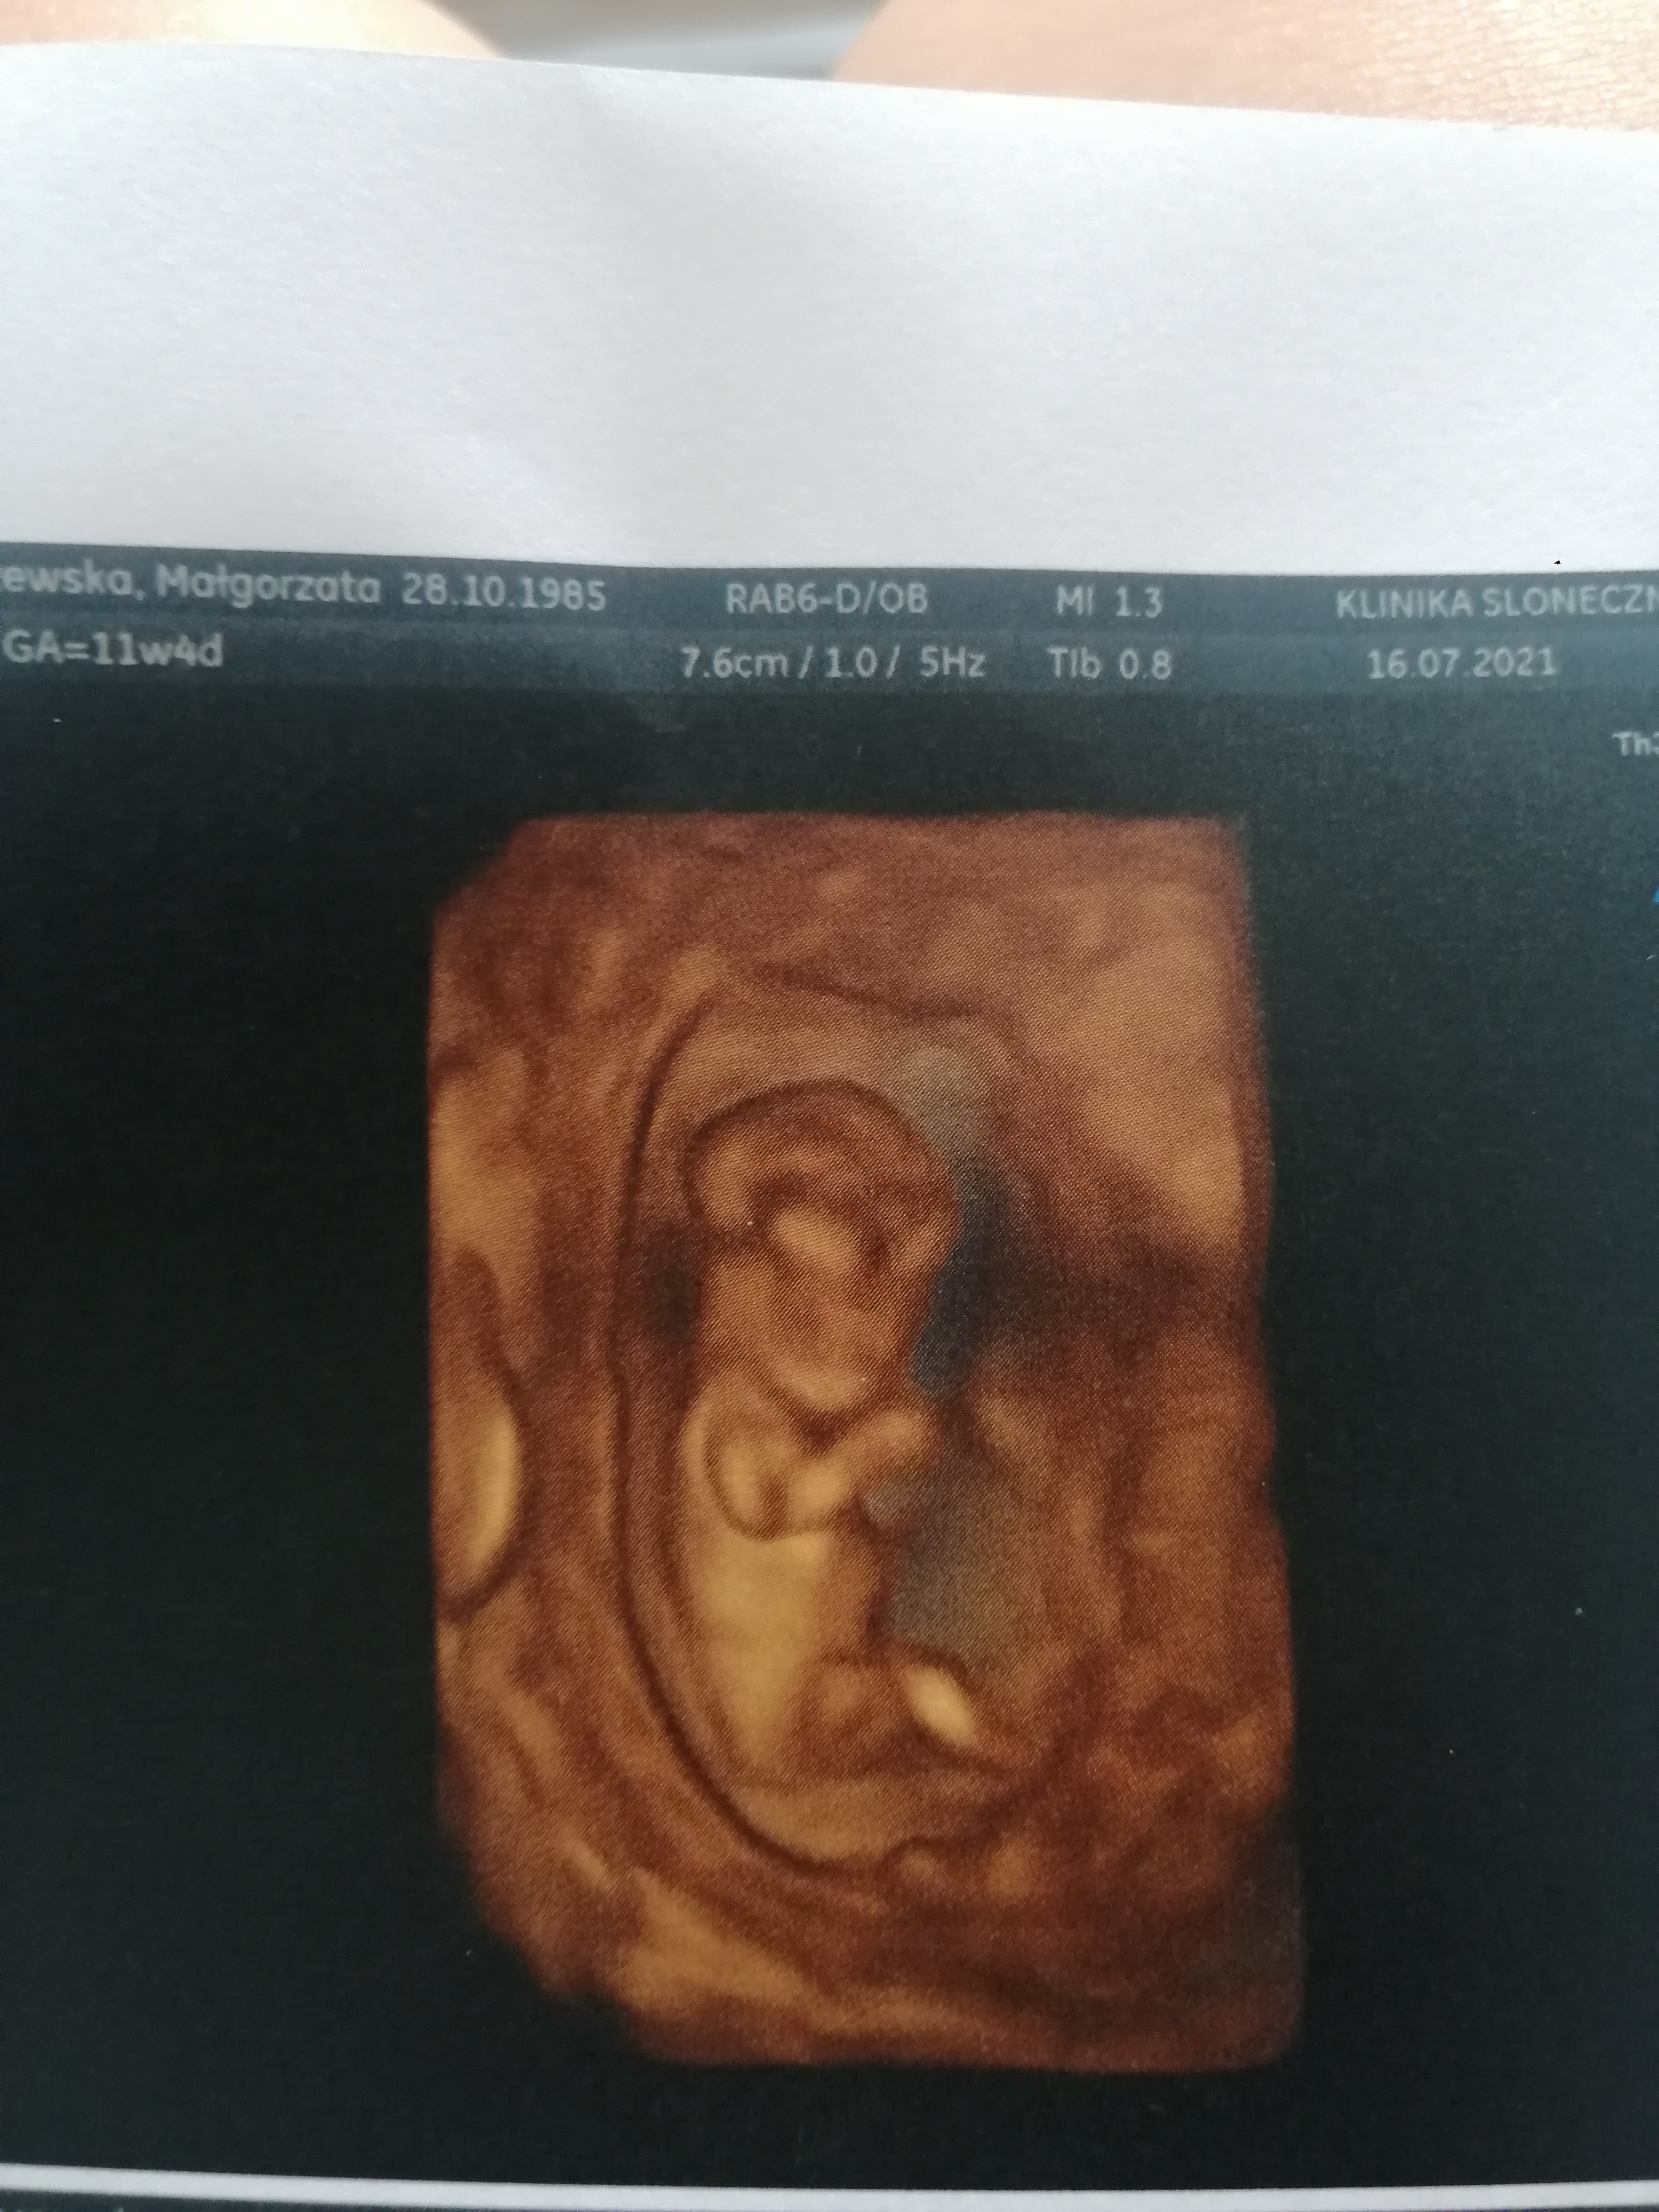

Hej ja juz jestem po prenatalnych.

Wszystko dobrze, pomiary wszystkie w normie, dzidzi fikalo jak szalone. Ma prawie 5cm. Krew oddana i czekam na wyniki. Ale i tak juz kamien z serca

• IMG_20210716_114424.jpg

IMG_20210716_114424.jpg

2,4 MB · Wyświetleń: 133